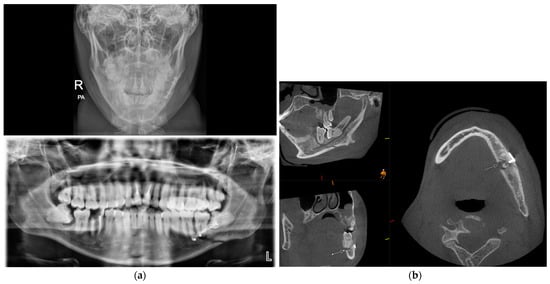

3.2. Cone Beam CT for Assessment of Mandibular Fractures

3.6. Cone Beam CT for Assessment Fractures of the Zygomatic Maxillary Complex and Midface